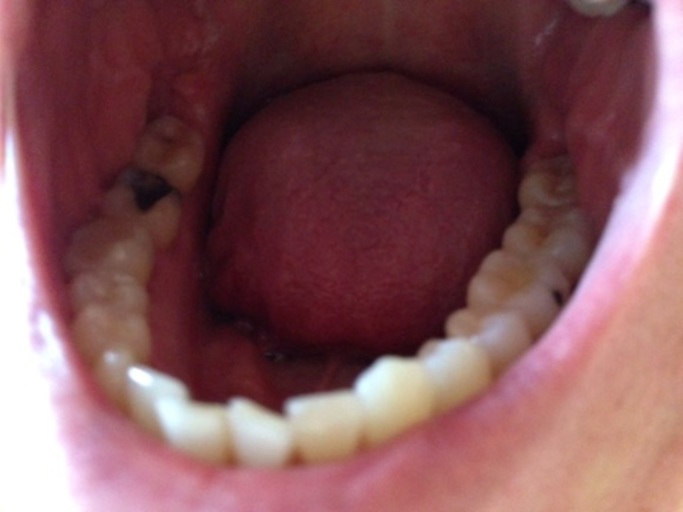

How to know if need a root canal?

I have swelling in my cheek. I have pain in my tooth and under my gum I have a large bump which I causing the swelling I think and it hurts and I want to know what it is and if I need a root canal? In the photo it is the molar with filling that you can see the most

I have swelling in my cheek. I have pain in my tooth and under my gum I have a large bump which I causing the swelling I think and it hurts and I want to know what it is and if I need a root canal? In the photo it is the molar with filling that you...